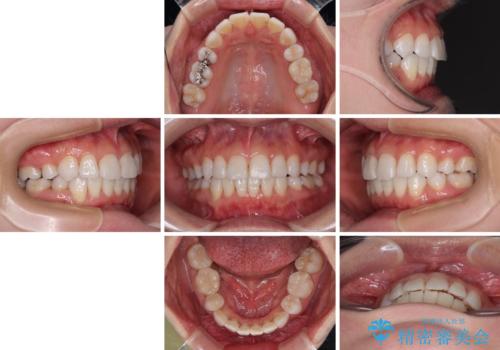

矯正治療の後戻り インビザラインで短期間矯正治療

- インビザライン・モデレート

- 8ヶ月

- 5-10回

- 上下前歯の後戻りを気にして来院された患者様です。

インビザラインでの治療を希望されていて、デコボコの程度が中等度であり、安価なパッケージにて対応可能と判断されたため、インビザライン・モデレートを用いて矯正治療を行うこととしました。

- 65万円(税込)費用は治療当時の料金となります